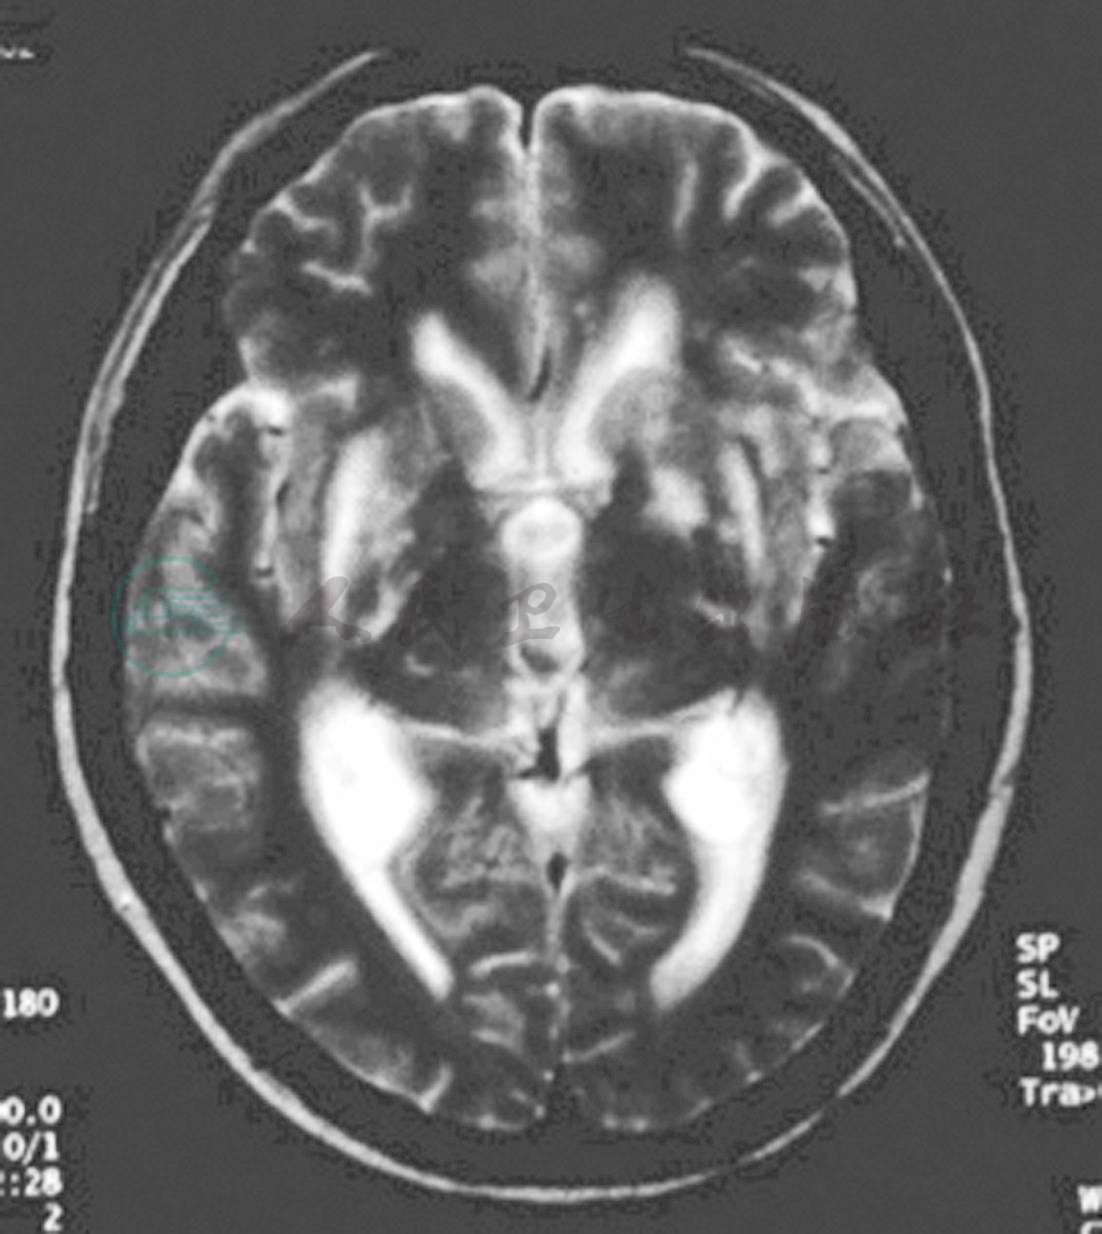

患者自2000年12月无明显诱因出现发热,最高38℃,午后明显,不伴畏寒、寒战、乏力、纳差,就诊外院查“血三系低,尿便(-),肝肾功能(-),骨髓穿刺(-),B超示“门脉增宽,脾大”,考虑“脾大,脾亢”。外院行脾切除术,病理不详。术后患者发热症状完全缓解。2001年5月患者再次出现发热,最高38℃,外院查:血红蛋白90g/L;ESR 108mm/h;IgG30.9g/L;CMV-Ab(+);骨髓穿刺:骨髓增生活跃,浆细胞8%;血尿轻链定量均高于正常;腹部CT:肝肿大,腹膜后淋巴结肿大。予多种抗生素治疗症状未好转,考虑不除外免疫病,予泼尼松40mg/d口服,发热症状完全缓解。完全停药后,再次出现发热,自行加量后可缓解症状,此后患者反复无规律自行口服泼尼松,可间断控制症状。2001年5月患者发热,口服泼尼松无缓解,伴头痛,持续,部位不定,停用泼尼松后出现高热,最高41.5℃,头痛加重,剧烈,伴恶心,呕吐,并逐渐出现反应迟钝,智能活动减退,活动力下降。腰穿脑脊液:细胞总数30×106/L,白细胞30×106/L,蛋白1.87g/L,氯化物114mmol/L,糖0.5mmol/L;血沉34mm/h; ENA谱: SSA+52kD; C-RP 192mg/L;外院查体:颈项强直,颏胸距2横指,查HIV、HBV、HCV抗体均阴性;查CSF(6月13日/7月 1日):压力50/120mmH2O,细胞总数22/6×106/L,白细胞11/0×106/L,蛋白110/94mg/dL,氯化物115.3/116.8mmol/L,糖4/50mg/dL,墨汁染色和抗酸染色阴性,真菌培养可见新型隐球菌。头CT及MRI(图1):双侧基底节病变,脑积水,局部脑膜强化。

隐球菌性脑膜炎基底节区的病变有一定特征性:约50%的隐球菌性脑膜炎可出现脑实质内多发小囊性改变,以基底节区明显,镜下改变为扩大的血管周围间隙中充满隐球菌,炎性细胞反应一般不明显。这种多发小囊性改变有些类似血管周围的筛空状态,由于血管周围间隙与蛛网膜相延续,因此这些病灶不是严格意义上的脑实质损害。

图1 头CT及MRI T2加权